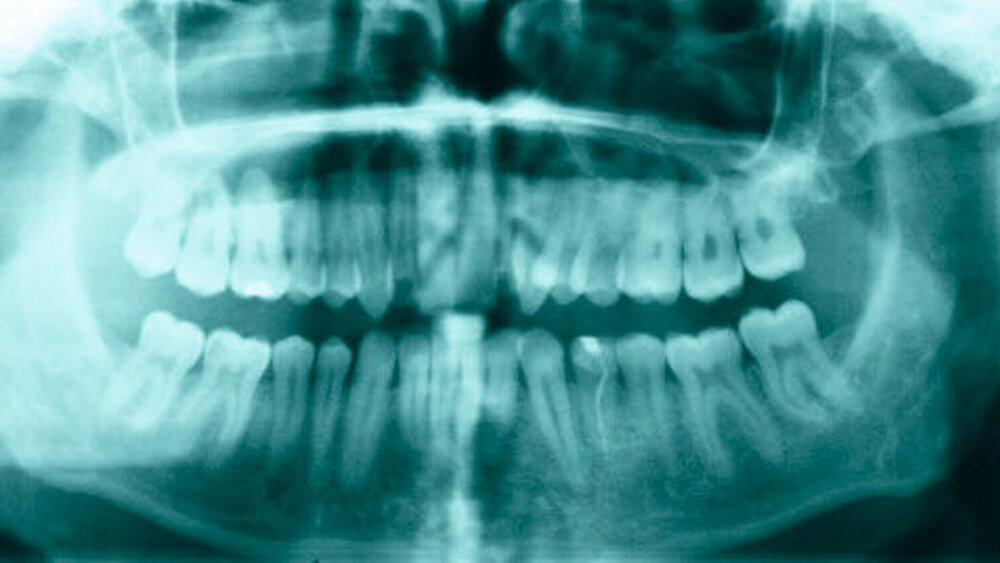

Bei der Befundung des Orthopantomogramms fielen hyperplastische, weit nach cranial extendierende Processus (Proc.) coronoidei beidseits auf (Abbildung 2).